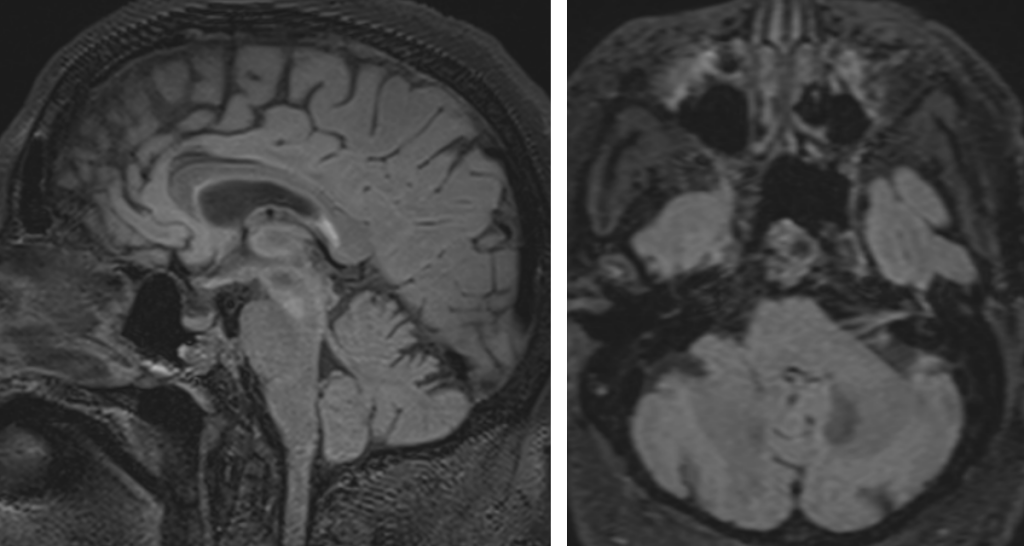

Figura 3: examinare IRM sagital şi axial FLAIR

Discuţie caz nr 45: Chisturile neuroenterice sunt leziuni de dezvoltare care au origine din endoderm, cel mai frecvent întâlnite în canalul rahidian, dar observate și în fosa posterioară și mai rar, supratentorial.